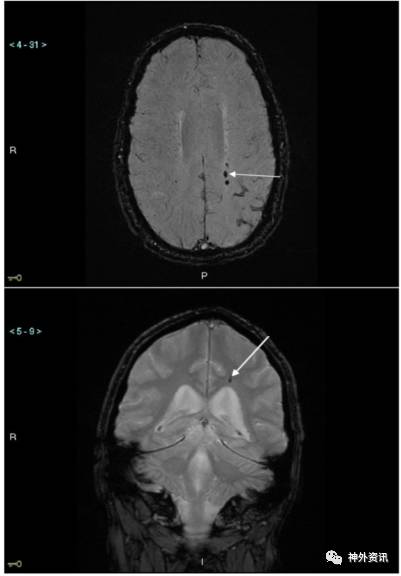

图1. SWI和T2*GRE显示同一患者顶叶微出血灶。上图为SWI图像,白箭头指示3个微出血灶;下图为T2*GRE图像,白箭头指示1个微出血灶。

结果显示,与T2*GRE序列相比,采用SWI序列检测到微小出血的数量几乎翻1倍,341个比179个(p<0.01)。病变多出现在额叶和颞叶。两种序列检测到的微出血数量在皮质与皮质下的分布非常接近;SWI序列:皮质185个比皮质下156个;T2*GRE序列:皮质96个比皮质下83个(图2)。